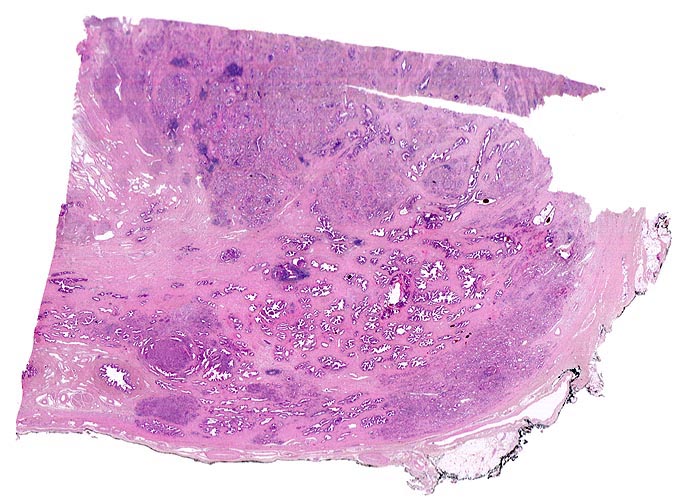

Morphologische Merkmale:

• Normale Prostatadrüsen mit grossen Lumina angeordnet in Läppchen. Das Epithel bildet Falten und besteht aus einer inneren hochprismatischen sekretorischen Zellschicht und einer äusseren Schicht flacher Myoepithelien.

• Herde kleiner Karzinomdrüsen ohne Basalzellschicht.

• Fehlende lobuläre Anordnung der Karzinomdrüsen.

• Konfluierende Drüsen bilden kribriforme Muster.

• Karzinomzellen mit stark erhöhter Kern-Zytoplasmarelation und hyperchromatischen Zellkernen mit grossen eosinophilen Nukleolen.

• Wenig differenzierte Karzinomanteile ohne erkennbare Drüsenbildung.

• Perineuralscheideninvasion.

• Links oben im Präparat finden sich Anteile der Samenblase mit polymorphem Epithel und gelben Lipofuszinpigmenteinlagerungen.

• Unterhalb der Samenblase sind von flachem Endothel ausgekleidete Lymphgefässe mit Karzinominfiltraten erkennbar (Lymphangiosis carcinomatosa).

• Der mit schwarzer Tusche markierte Resektionsrand in der unteren Hälfte des Präparates ist tumorfrei.